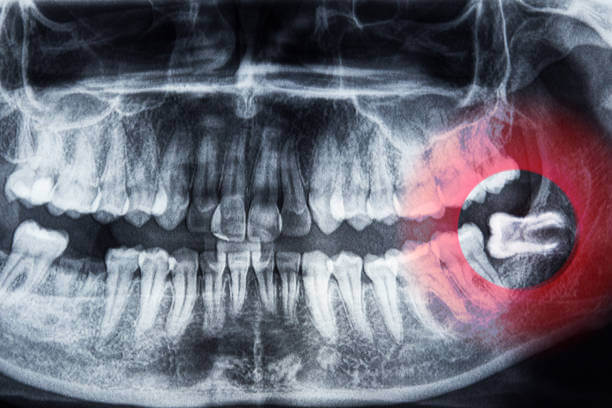

사랑니는 대부분 치아 뒤쪽에 위치해 제대로 자라지 못하고 염증, 충치, 잇몸질환 등을 유발합니다. 이럴 경우 건강보험 적용이 가능하며, 일부는 실손의료보험(실비보험) 청구도 가능합니다.

- 매복 사랑니 발치로 잇몸 절개, 골삭제, 봉합이 필요한 수술코드가 발생한 경우

- 통증·염증 등의 질병 사유로 인해 발치가 의학적으로 필요한 경우